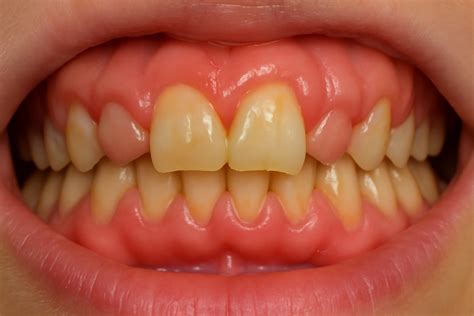

- Enrojecimiento e inflamación: Las encías afectadas por la hiperplasia gingival suelen presentar enrojecimiento e inflamación. La encía marginal mostraba una inflamación generalizada y se encontraba muy tumefacta.

Se constató una presencia generalizada de depósitos duros y blandos de placa dental principalmente en las zonas interdentales y de cálculo en todo el sector anterior. La encía marginal mostraba una inflamación generalizada y se encontraba muy tumefacta. Las profundidades de sondaje se encontraban principalmente entre los 5 mm y los 9 mm y, en puntos aislados, eran de 10 mm. El nivel de inserción oscilaba entre los 4 mm y los 6 mm; en algunos puntos, era de 7 mm. No se observaron afectaciones de furca. La paciente presentaba halitosis.